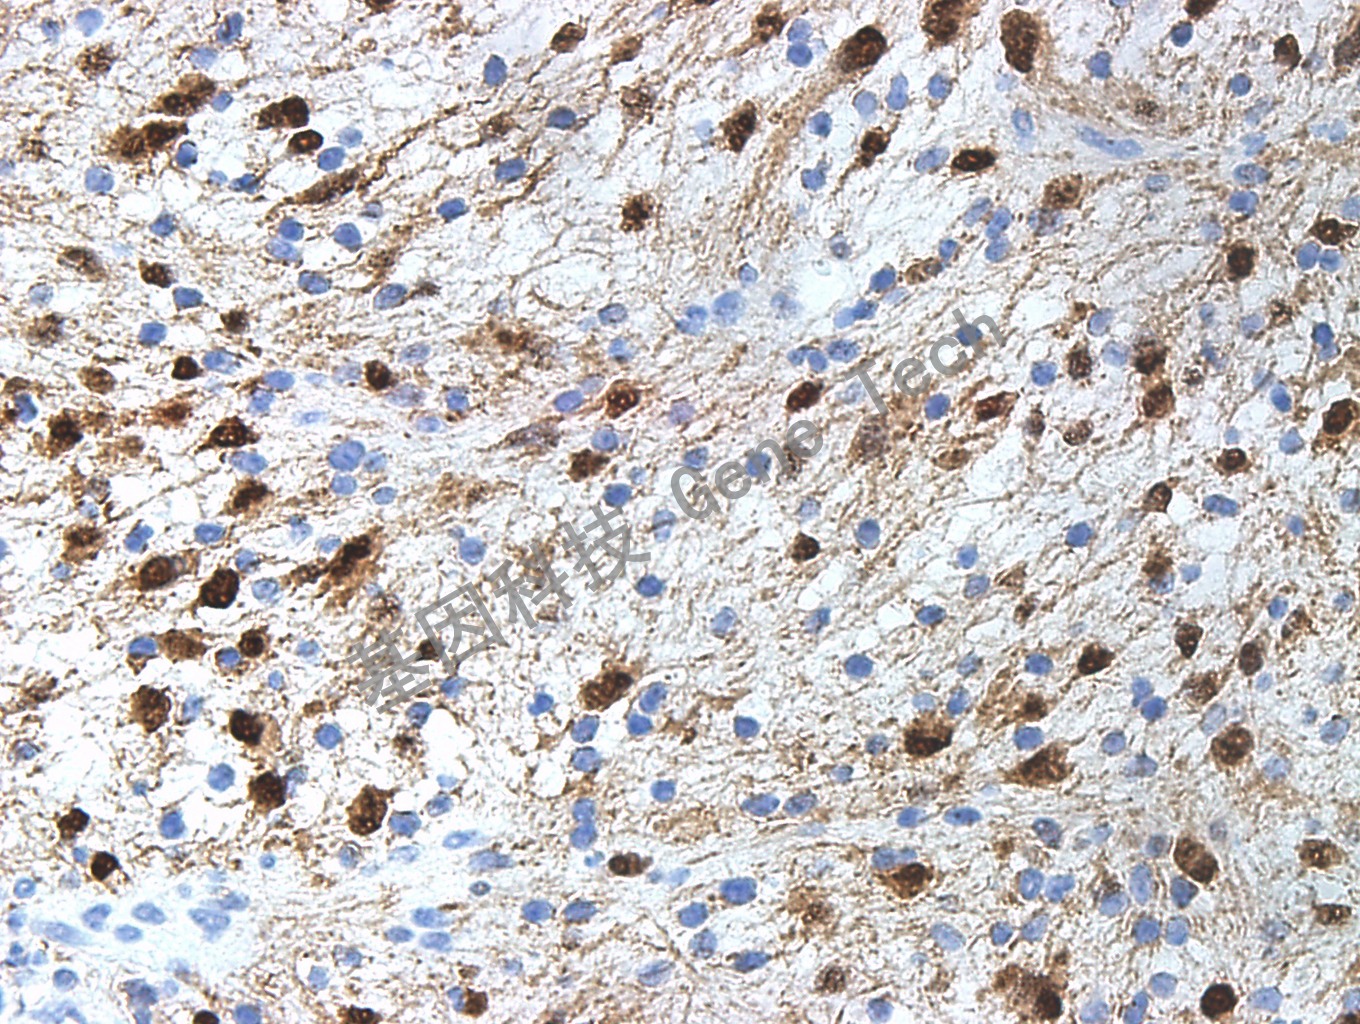

| 克隆號(hào):GR511 | 種屬:兔 | 適用染色系統(tǒng):GTvisionTM |

| 預(yù)處理:高pH熱修復(fù) | 陽(yáng)性部位:細(xì)胞漿/細(xì)胞核 | 陽(yáng)性對(duì)照:黑色素瘤 |

| 簡(jiǎn)介:S-100是由α鏈和β鏈組成的二聚體。廣泛存在于間葉源性細(xì)胞和淋巴造血組織,如膠質(zhì)細(xì)胞、黑色素瘤細(xì)胞、軟骨細(xì)胞、施萬(wàn)細(xì)胞、指突狀網(wǎng)狀細(xì)胞和朗格漢斯細(xì)胞。在診斷黑色素瘤種比較有價(jià)值,在轉(zhuǎn)移性黑色素瘤中比HMB-45表達(dá)較多;鑒別軟骨內(nèi)腫瘤和其他骨性腫瘤;鑒別硬化性腺病和乳腺的管狀腺癌;鑒別佩吉病和上皮擴(kuò)展性黑色素瘤。 | ||

| 神經(jīng)鞘瘤石蠟切片,用 S-100(GZ0311)染色,細(xì)胞漿/細(xì)胞核陽(yáng)性,DAB 顯色。 | ||